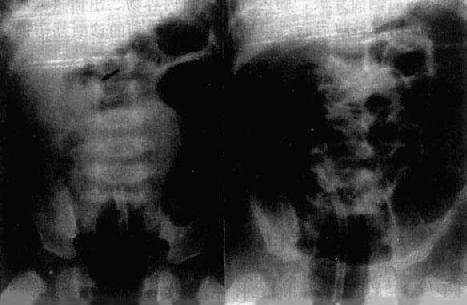

闭袢梗阻型乙状结肠扭转较常见,即近端与远端各有一梗阻点。诊断大多可由平片作出,表现如下:①闭袢的乙状结肠曲明显扩大,横径可达20cm以上,自盆腔上升至中腹部甚至可达上腹和膈下;②扩大的乙状结肠曲常呈马蹄铁状,其圆顶向上,两肢向下并拢而达盆腔,内含大量气体和液体;③上述乙状结肠曲的肠壁显影如三条纵行致密线,向下方梗阻点集中(图4-1-6)。如平片不曲型需作钡灌肠,可见直肠乙状结肠交界处阻塞,上端逐渐尖削如鸟嘴状,有时可见到旋转状粘膜皱襞。这是乙状结肠扭转的特征性表现(图4-1-6)。

图4-1-6 乙状结肠扭转